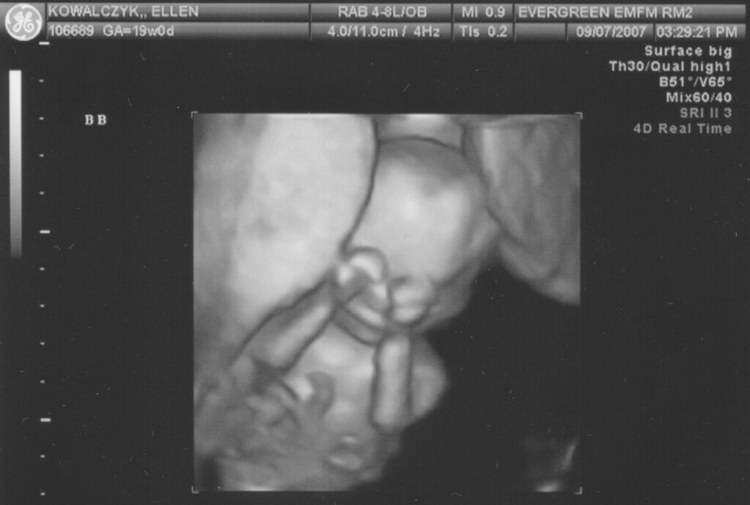

– Ultrasonido 3D. Esta prueba muestra una imagen realista de un bebé por nacer.

Emma Kowalczyk - 19 weeks - 3D ultrasound - She was a little… - Flickr– Abdomen y estómago